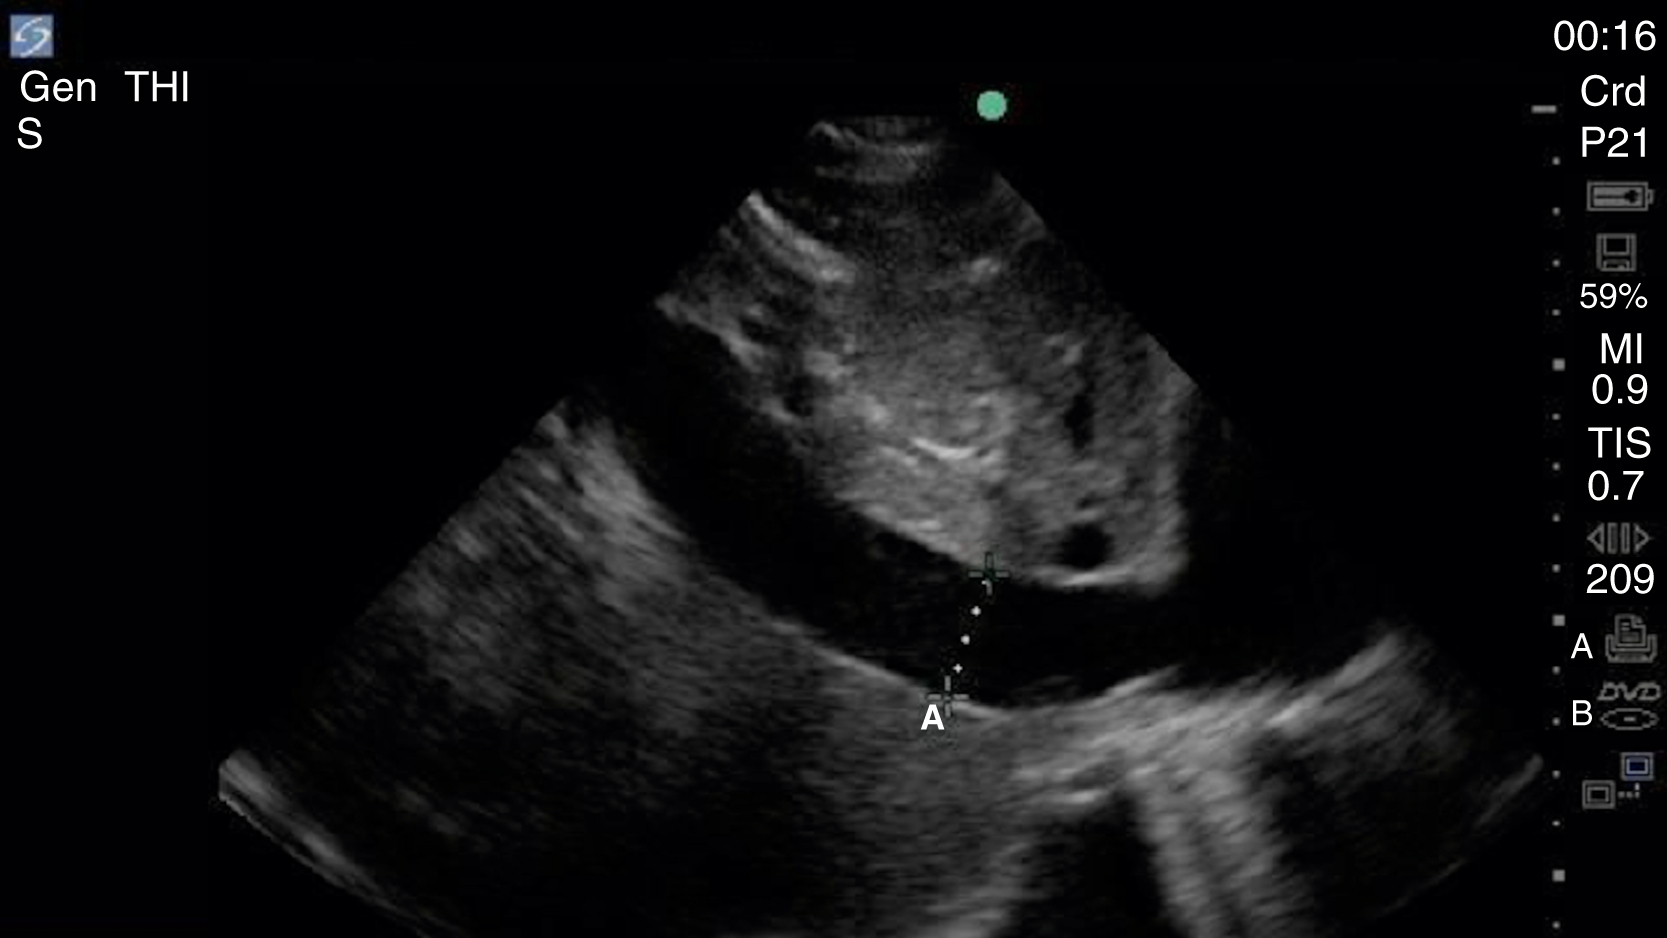

Pericardial fluid is typically anechoic, although it can contain internal echoes in cases of pericardial hemorrhage or infection. Large pericardial effusions are usually circumferential but can be loculated. As a result, assessment for pericardial effusion should include multiple views, when feasible, to confirm diagnosis and to avoid mistaking the epicardial fat pad for a pericardial effusion. Although cardiac tamponade is a clinical diagnosis, there are several suggestive echocardiographic features, including diastolic collapse of the RV ( Video e3.9 ), loss of respiratory variation of the IVC ( Fig. e3.11 ), and transvalvular flow velocity paradoxus.

Fig. e3.11

Plethoric IVC showing where to take a measurement.